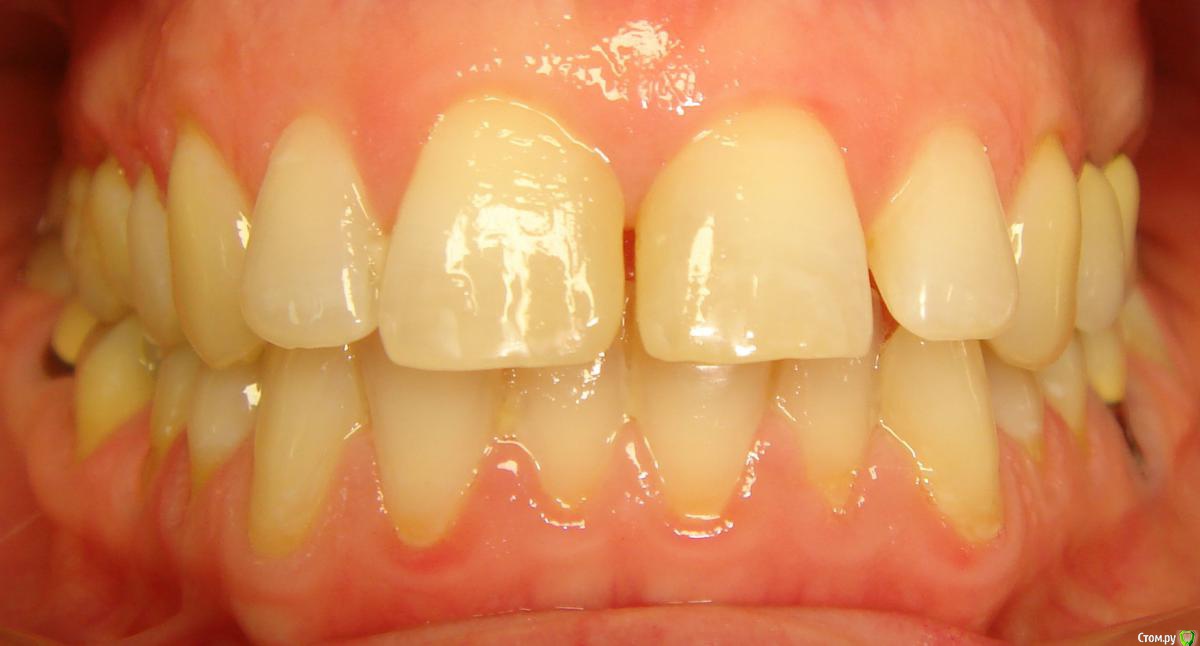

Opdihatop Опубликовано 16 апреля, 2017 Автор Поделиться Опубликовано 16 апреля, 2017 Она сама то что хочет Черные треугольники заполнить и рецессии убрать. Ссылка на комментарий

Brigita Опубликовано 16 апреля, 2017 Поделиться Опубликовано 16 апреля, 2017 Черные треугольники заполнить и рецессии убрать. я вот чего то не понимаю наверно.. где треугольники, которые она хочет убрать? я вижу диастему, трему 22-21, кариес 11-12, многочисленные рецессии, плохие ортопедические коронки, неправильно выполненные вкладки ( а может правильно? я не ортопед), скученность нижних зубов. А вообще вот интересно - в каком возрасте максимально возможно расширение на SARPE, у кого какой опыт? Ссылка на комментарий